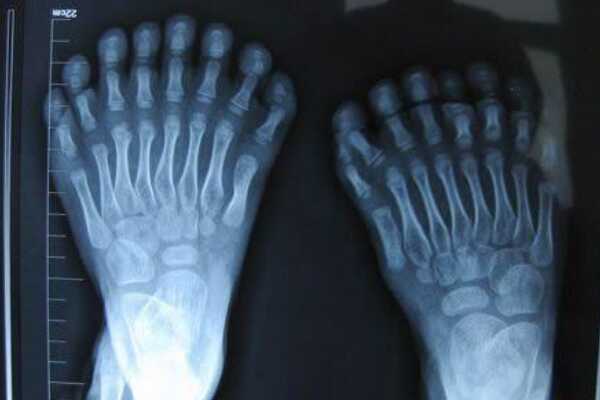

对于大多数人来说,张开双手最多数到十,但来自印度的一个小男孩张开手掌,可以一直数到14,再张开脚趾就更是让人大吃一惊,竟然多达20个,也就是说他总共有34个手指和脚趾,略微超过之前我国的鹏鹏小男孩,就这样他成为了世界上手指脚趾最多的人。

这个印度小男孩之所以拥有14根手指和20根脚趾,主要是因为基因问题导致的多指畸形,因此是虽然他是这个世界上手指脚趾最多的人,但他的父母为此非常的担心,他的日常生活可能会受到困扰和遭遇麻烦,这就像世界上最高的儿童一样,身体上的特异部分会带来别人的异样眼光,可能会给孩子的心里产生影响。